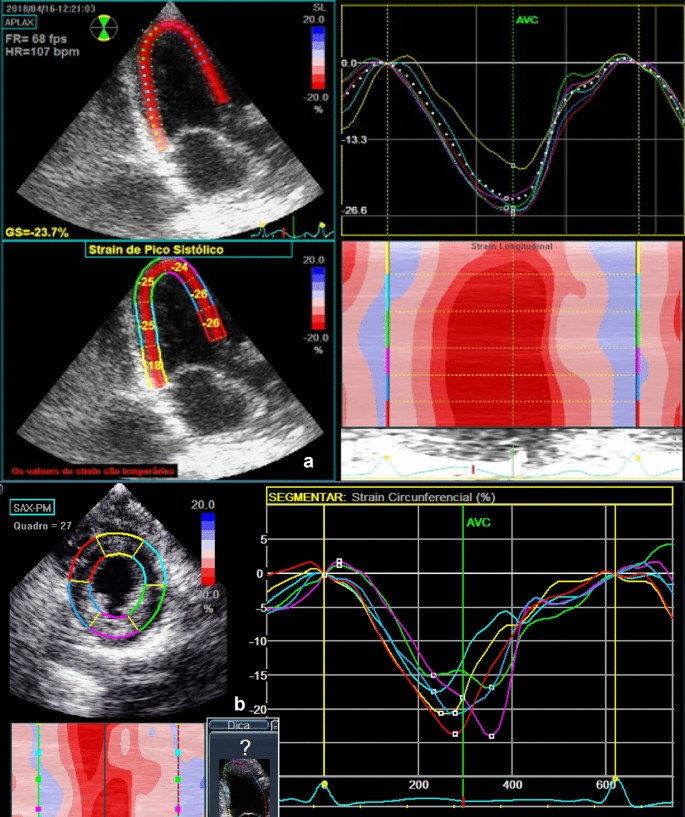

For strain assessment, two-dimensional grey-scale images were acquired in the apical four, three and two-chamber views, with a frame rate of 60–80 fps. In the same way the acquisition of the images in the parasternal window was performed, transverse short axis of the left ventricle in its 03 main cuts: basal, middle and apical. The time "systolic event" was determined by marking the opening and closing moments of the aortic valve. Three cardiac cycles were digitally stored and analyzed using the EchoPAC program BT10 (GE Vingmed Ultrasound AS) (Fig. 1).

Evaluation through two-dimensional speckle tracking

Patients in pre-transplant group had a significant reduction in the parameters of left ventricular longitudinal myocardial deformation as shown in Table 5. The global longitudinal strain (GLS) of left ventricle was significantly lower in pre-transplant patients (−20.86 ± 2.59 vs. −22.79 ± 1.52%, p = 0.001) than controls. When analyzed separately from each window, a significant reduction of longitudinal strain was observed in the three-chamber (APLAX) (−20.38 ± 3.08 vs. −22.40 ± 1.52%, p = 0.005) and in the apical four chambers (4C) (−21.10 ± 3.05 vs. −23.57 ± 2.64%, p = 0.001). The GLS of the right ventricle also showed a significant reduction in the pre-transplant group (−23.91 ± 4.34 vs. −26.45 ± 3.65%, p = 0.017). The apex radial strain was significantly lower in pre-liver transplant patients (29.84 ± 11.12 vs. 35.14 ± 8.63, p = 0.044), as well as the radial strain at the level of the papillary muscle (25, 28 ± 8.57 vs. 31.75 ± 5.36, p = 0.001) and the overall radial strain (27.05 ± 6.92 vs. 31.54 ± 4.23, p = 0.004). The circumferential strain at the level of the papillary muscle was significantly lower in pre-liver transplant patients (−23.89 ± 4.88 vs. −26.55 ± 3.58, p = 0.019) as well as the global circumferential strain (−25.76 ± 4.42 vs. −27.84 ± 3.38, p = 0.045).

Post-liver transplant patients also showed a significant reduction in the parameters of left ventricular longitudinal myocardial deformation as shown in Table 5. Left ventricular GLS was significantly lower in patients after liver transplantation (−21.47 ± 2.25 vs. −22.89 ± 2.30%, p = 0.019) comparing to controls. When analyzing each window separately, a significant reduction of longitudinal strain was observed in the APLAX (−20.70 ± 3.76 vs. −23.33 ± 2.92%, p = 0.004) and in the 4C (−21.30 ± 2.9 vs. −23.01 ± 2.50%, p = 0.02). The GLS of the right ventricle also showed a significant reduction in the post-transplant group (−24.59 ± 3.53 vs. −27.60 ± 3.35%, p = 0.001) as well as the radial strain at the level of the papillary muscle (27.85 ± 6.90 vs. 32.14 ± 6.42, p = 0.015) the radial strain at the level of the mitral valve (25.66 ± 6.57 vs. 29.99 ± 5.36, p = 0.007) and global radial strain (27.58 ± 4.90 vs. 31.13 ± 4.89, p = 0.007).